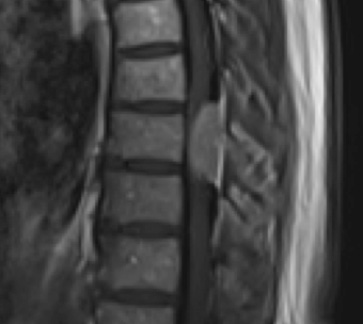

Preoperative MRI T2 demonstrating obstruction of CSF around the cord (blue arrow), resulting from the tumor (red arrow)

Preoperative MRI T1w demonstrating a large enhancing tumor with severe cord compression